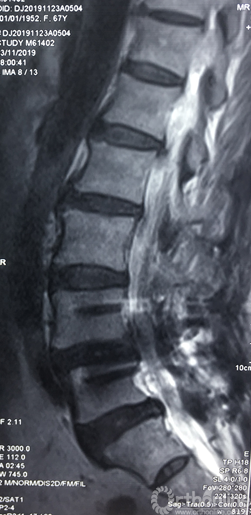

术前腰椎核磁共振矢状面